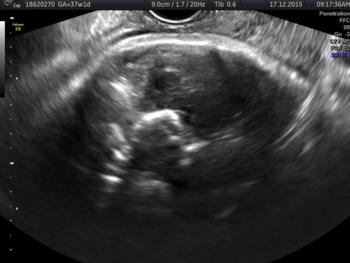

In a third study, ultrasound and fetal MRI were performed on pregnant patients with Zika virus infection at different gestational ages. Once the babies were born, they underwent ultrasound, CT and MRI. The researchers then created 3-D virtual and physical models of the skulls. More than half the babies had microcephaly, brain calcifications and loss of brain tissue volume, along with other structural changes.

"The emergence of Zika virus in the Americas has coincided with increased reports of babies born with microcephaly," said study author Heron Werner Jr., M.D., Ph.D., from the Department of Radiology at Clínica de Diagnóstico por Imagem. "An early diagnosis may help in treating these babies after birth. Moreover, the knowledge of abnormalities present in the central nervous system may give hints about the pathophysiology of the disease."